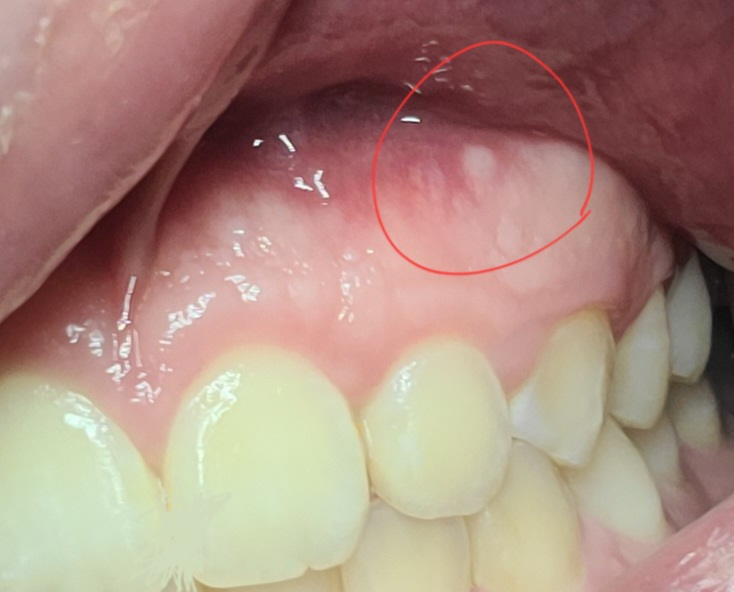

잇몸에 하얀게 생겼어요 이게뭔가요?

치아 위쪽 잇몸에 하얀게 생겼어요

처음에 구내염 인줄 알았는데 구내염은 건들기만해도 아플정도 인데 그정도는 아니고 평소 느낀 염증이랑은 다른 느낌이더라고요

치아뼈가 튀어나온것 같기도하고 만지면 저부분만볼록 나온느낌이 들고 건들면 아주 약~간 통증있는 정도

저게 뭘까요?